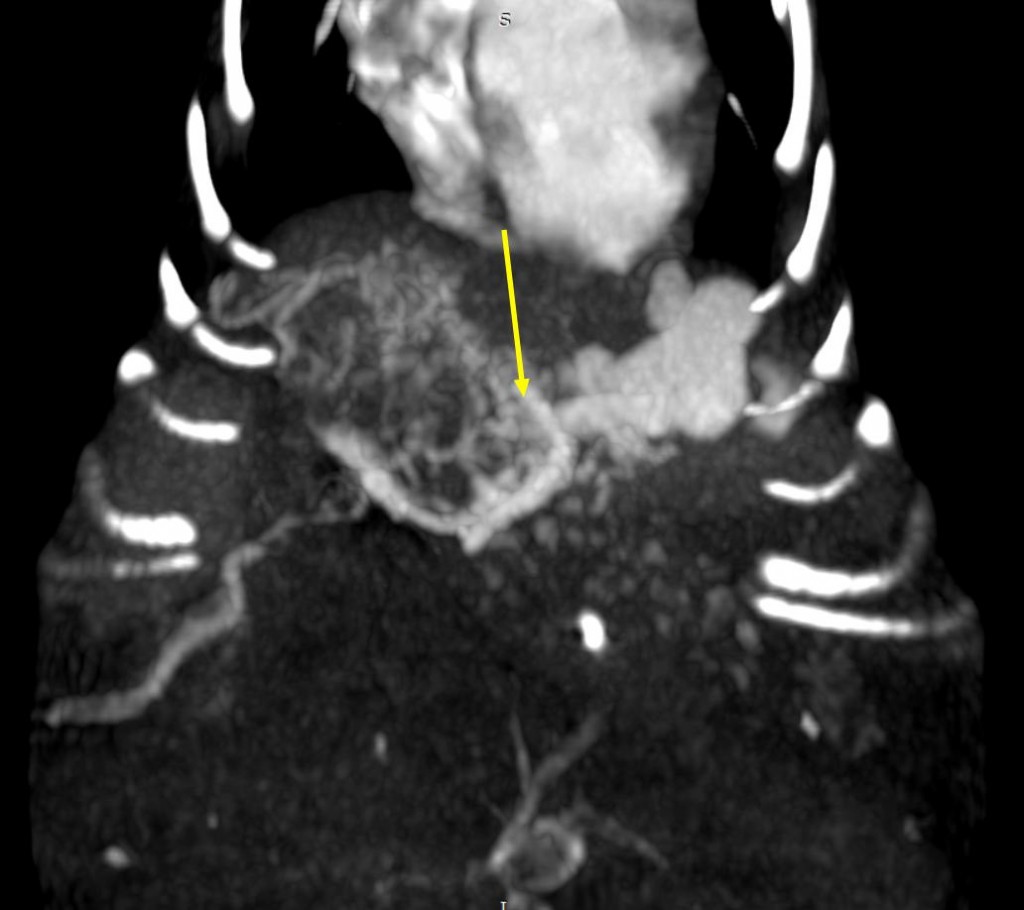

Диагностика печеночных АВМ осуществляется с применением КТ-ангиографии, выявляющей сосудистую сеть (или «гнездо»), образованную ветвями приносящей печеночной, гастродуоденальной, левой желудочной и другими артериями, через которую происходит слияние с воротной веной (рис. 3). Артериальная фаза является самой важной в идентификации приносящих ветвей артериовенозной мальформации. АВМ имеют тенденцию изменяться со временем, в связи с этим КТ-ангиографию рекомендуют проводить как можно ближе к дате планируемого хирургического вмешательства.

Для эмболизации артериовенозной мальформации печени (рис. 4) у 5-месячной собаки весом 2,7 кг автор статьи использовал спирали, а также коллагеновую губку и клей (3M Vetbond). Сосудистый доступ осуществлялся через бедренную артерию, в которую был установлен интродьюсер 4 Fr (рис. 5). Катетеризация печеночной артерии проводилась катетером Cobra, 4 Fr (рис 6.) В трех наиболее крупных ветвях приносящих артерий были размещены спирали, однако сильный ток крови в сосудах «гнезда» после размещения спиралей сохранялся. Из коллагеновой губки, контрастного вещества («Ультравист») и физраствора была приготовлена смесь в объеме 1,0 мл, которая была введена через катетер 4 Fr, размещенный в области бифуркации приносящих артерий «гнезда». Это снизило риск миграции клея в портальную вену и нецелевой эмболизации. После этого по катетеру был введен клей 3M Vetbond. По окончании манипуляции в сосудах «гнезда» мальформации не отмечалось наличия тока крови.